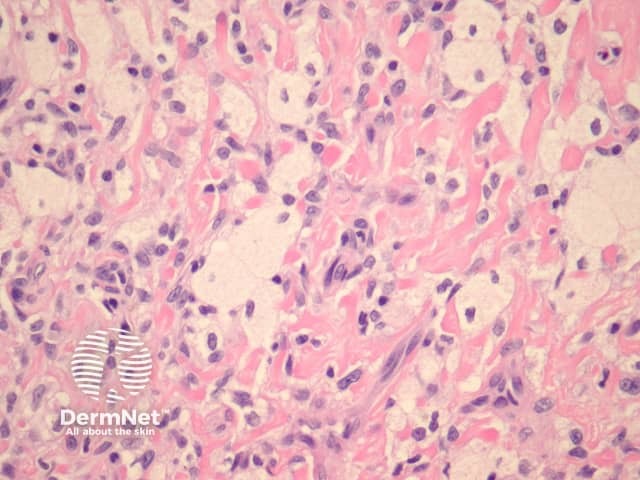

Histologically, there are cleft-like haemorrhagic spaces within the centre of the aneurysmal dermatofibroma that mimic vessels but lack an endothelial lining. The tumour itself tends to be fairly cellular (figure 7, 8). Haemosiderin deposition may be an additional feature. Aneurysmal dermatofibroma may be mistaken for a vascular tumour, however, clues to the diagnosis include surrounding features of dermatofibroma, and endothelial cell markers are positive in normal vessels only and not the aneurysmal spaces.